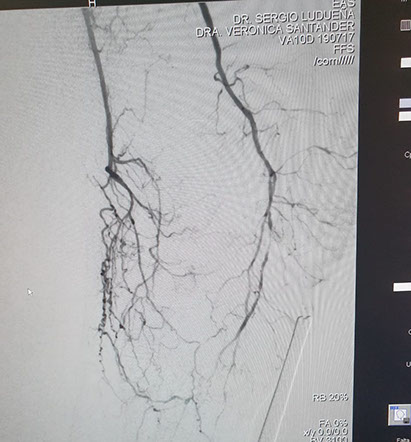

El Dr Sergio Raul Ludueña Jefe del Servicio de Hemodinamia de INCOR nos comentó sobre procedimiento realizado en el día de ayer en en el Servicio. "Queremos compartir con ustedes si bien no es un caso coronario , es un paciente obeso mórbido, diabético, con amputación supracondilea de miembro inferior izquierdo hace 3 años y actualmente con isquemia critica de miembro inferior derecho, con oclusión de ambas tíbiales y sin circulación en el pie".

Se realizó un abordaje híbrido con el Dr. Alejandro Flores, y se re canalizó ambas arterias tíbiales. Procedimiento inédito en nuestra provincia.

Las imágenes siguientes son previas al procedimiento y posterior se ve ambas arterias tíbiales permeables, y circulación en el pie